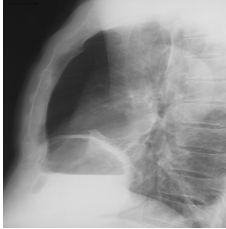

Primitiv, sau consecutiv unei bronsite cronice, emfizemul pulmonar se traduce radiologic prin urmatoarele semne:

hipertransparenta pulmonara (hiperinflatia) difuza, generalizata sau localizata;

coborarea si aplatizarea cupolelor diafragmatice;

orizontalizarea coastelor cu cresterea dimensiunilor spatiilor intercostale;

hernierea plamanilor prin spatiile intercostale, astfel ca vor avea contur festonat;

cord verticalizat, in picatura;

bule apicale si inferioare;

largirea spatiului clar retrosternal;